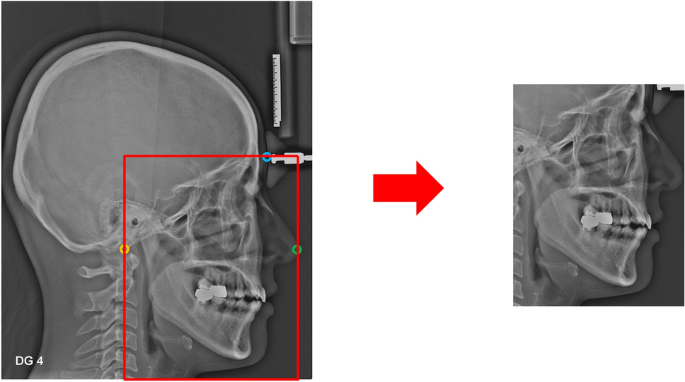

The modality differences between Lateral A and Lateral B images existed in the image magnification and resolution as well as the standardization format of image acquisition, which were contrasted by a histogram (Fig. 1). To unify the field of view (FOV) of two image modalities, all images were cropped to include all the potential critical regions of interests (ROIs) predisposing to OSA. Three cephalometric landmarks were automatically extracted with the previously developed landmark-detection algorithm to generate the consistent cropping boundaries: Basion, Glabella, and Pronasale points (Fig. 2)22. The accuracy of each landmark selected by algorithm is 0.76 ± 1.06, 1.36 ± 1.08, and 0.60 ± 0.46 mm, respectively22. The landmark position selected by algorithm was not modified for cropping. In addition, when resizing to the input shape, the aspect ratio of the original image was maintained to minimize the distortion of the actual image information. For data augmentation, image rotation was applied in a range of − 15° to 15°, and horizontal flip, CLAHE (Contrast Limited Adaptive Histogram Equalization) were applied randomly with a probability of 50%.